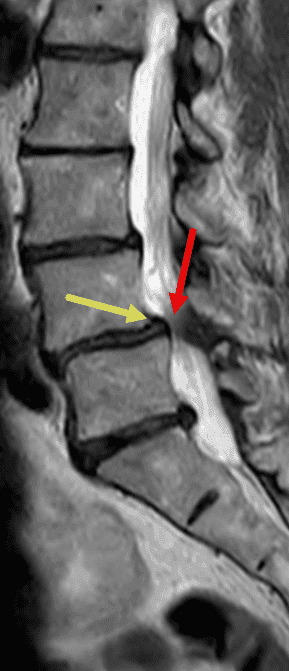

Claudication radiculaire bilatérale d'apparition progressive chez une patiente de 65 ans.

Présentation classique d'un canal lombaire rétréci (flèche rouge) en L4-L5, d'origine mixte : étalement discal, zygarthrose bilatérale (flèches vertes) avec épaississement des ligaments jaunes (flèche bleue), et antélisthésis de grade I de L4 (flèche jaune).

Sagittal T2